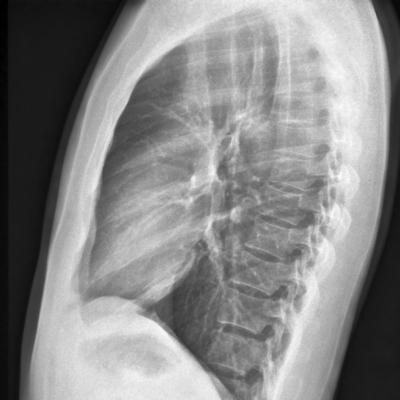

In 2021, the WHO updated its chest x-ray screening recommendations for TB to include computer-aided detection (CAD) and set a performance bar of 90% sensitivity and 70% specificity for clinical implementation of algorithms.

Currently, there are five commercial AI algorithms approved for detecting TB as well as other abnormalities on chest x-rays: qXR, CAD4TB, Lunit Insight CXR, InterRead DR Chest, and JF CXR-1, she added. These algorithms have performed well in other studies in different populations, yet few studies have evaluated their performance in sensitive populations such as patients with HIV, Sanjase said.

In this study, the researchers evaluated Google AI TB in adults who had symptoms suggestive of TB, who were close contacts of TB patients, or who were newly diagnosed with HIV. They enrolled 1,932 patients at three clinical sites. Of the 1,807 patients with a definitive TB status, 641 (35%) were HIV positive and 190 (11%) were TB positive.